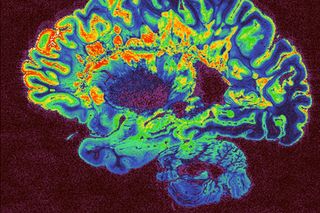

The new study, led Dr. Julie Bakker from the University of Liège, Belgium, and her colleagues from the Center of Expertise on Gender Dysphoria at the VU University Medical Center, the Netherlands, included both adolescent boys and girls who had experienced distress from identifying with a gender other than their biological sex (a state known as gender dysphoria). Through MRI scans, the team assessed brain activation patterns in response to a pheromone known to produce gender-specific activity.

They found the pattern of brain activation in both transgender adolescent boys and girls more closely resembled that of their gender identity among non-transgender boys and girls. In addition, adolescent transgender girls with gender distress showed a male-typical brain activation pattern during a visual/spatial memory exercise. Finally, some brain structural changes were detected that were also more similar, but not identical, to those typical of the desired gender of boys and girls distressed about their gender.